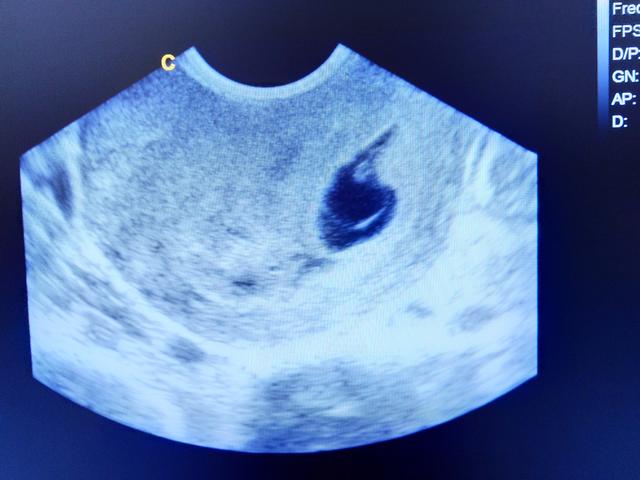

Eine leere Fruchthöhle kann bei einer Ultraschalluntersuchung festgestellt werden, wenn sich in der Gebärmutter keine Embryonalanlagen entwickelt haben. Dies wird oft als Windei bezeichnet. Es handelt sich dabei um eine Art Fehlentwicklung, bei der sich nur die äußere Zellschicht der Keimblase gebildet hat, jedoch kein Embryo vorhanden ist.

Wenn bei einer Ultraschalluntersuchung festgestellt wird, dass sich in der Fruchthöhle kein Embryo entwickelt hat, handelt es sich um ein Windei. Dies bedeutet, dass sich nach der Befruchtung der Eizelle zwar die äußere Zellschicht der Keimblase gebildet hat, aber die Embryonalanlagen fehlen vollständig.

Eine leere Fruchthöhle in der Ultraschalluntersuchung kann ein Anzeichen dafür sein, dass die Schwangerschaft nicht wie erwartet verläuft. Wenn bei einem positiven Schwangerschaftstest keine embryonalen Strukturen in der Fruchthöhle sichtbar sind, spricht man von einem „Windei“. Dabei hat sich zwar die äußere Zellschicht gebildet, aber es fehlen die Embryonalanlagen. In solchen Fällen kann sich die Schwangerschaft nicht weiterentwickeln.